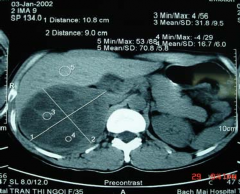

Hình 3.7: U tủy không chế tiết; Bệnh nhân só 29

Hình 3.8: U tủy có kích thước lớn

(10,8cm); Bệnh nhân số 6

Hình 3.9: U vỏ chế tiết kích thước nhỏ

(1,4cm); Bệnh nhân số 80